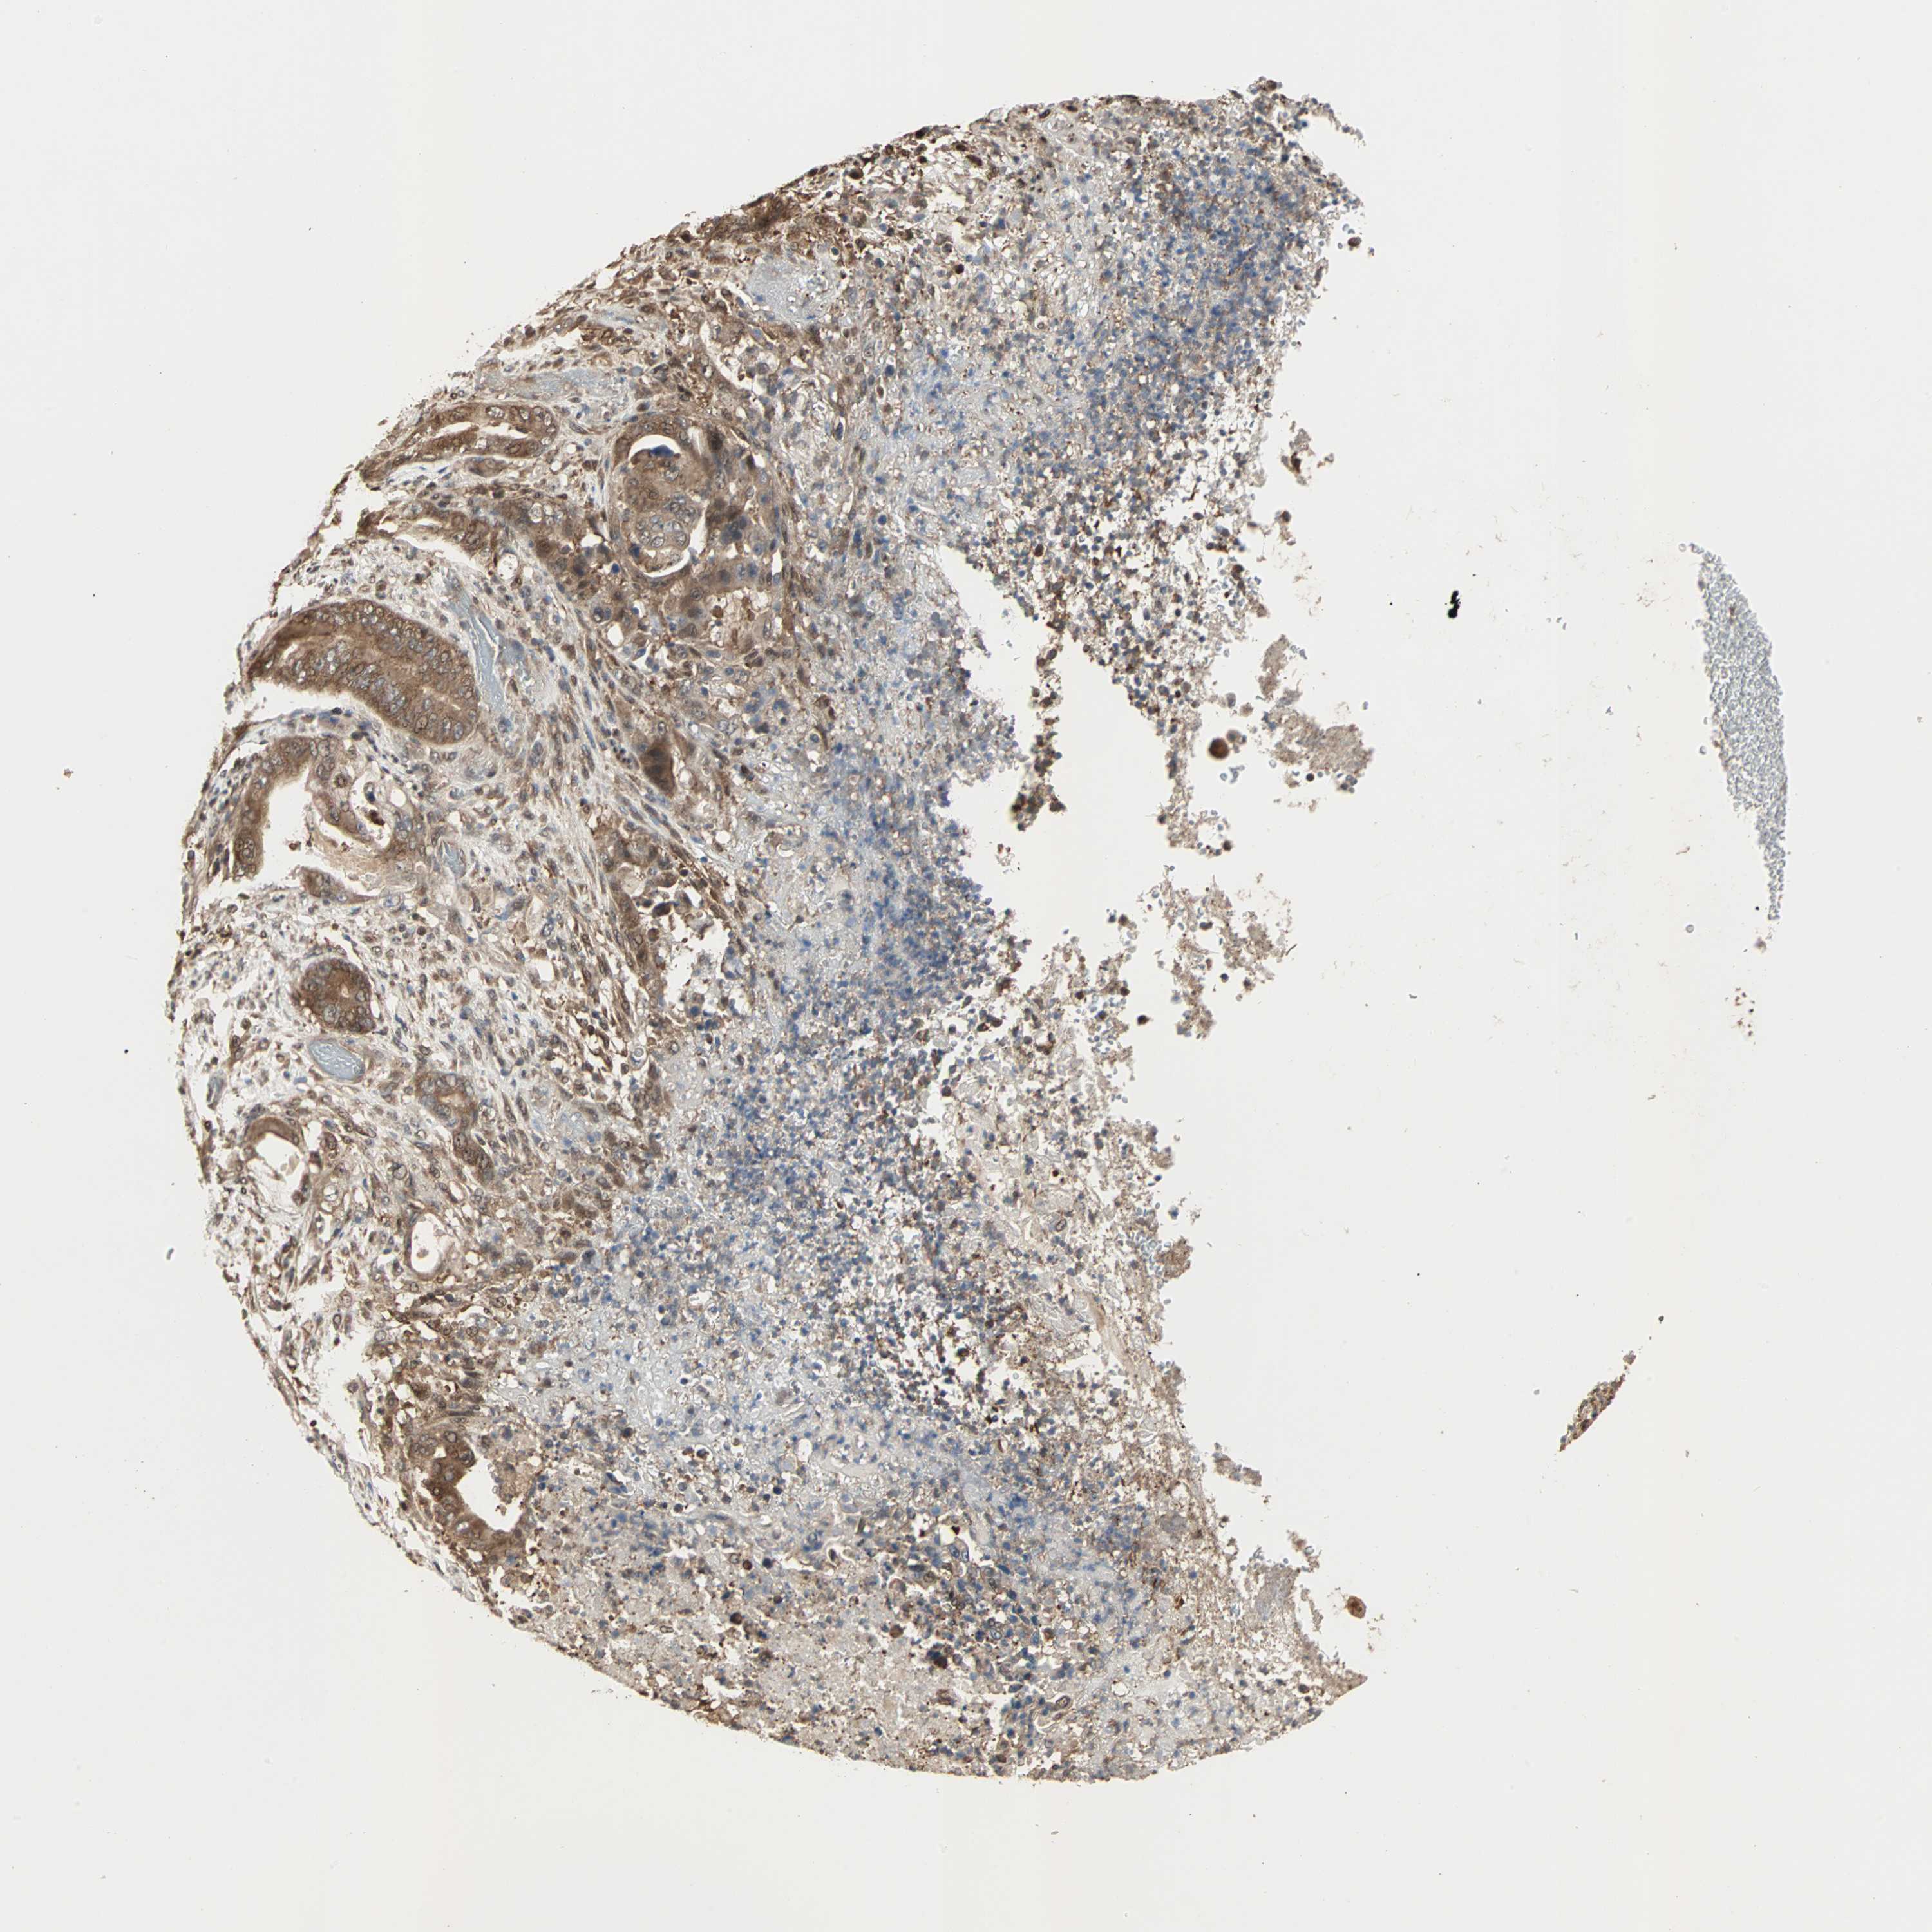

STOMACH CANCER - Protein expressioni

A mouse-over function shows sample information and annotation data. Click on an image to view it in a full screen mode. Samples can be filtered based on level of antibody staining by selecting one or several of the following categories: high, medium, low and not detected. The assay and annotation is described here.

Note that samples used for immunohistochemistry by the Human Protein Atlas do not correspond to samples in the TCGA dataset.

Antibody stainingi

Antibody staining in the annotated cell types in the current human tissue is reported as not detected, low, medium, or high, based on conventional immunohistochemistry profiling in selected tissues. This score is based on the combination of the staining intensity and fraction of stained cells.

Each image is clickable and will lead to virtual microscopy that enables deeper exploration of all samples and also displays staining intensity scores, fraction scores and subcellular localization as well as patient and tissue information for each sample.

Antibody HPA007716

Staining

High

Medium

Low

Not detected

Intensity

Strong

Moderate

Weak

Negative

Quantity

>75%

75%-25%

<25%

None

Location

Nuclear

Cytoplasmic/membranous

Cytoplasmic/membranous,nuclear

Adenocarcinoma, NOS

Adenocarcinoma, High grade